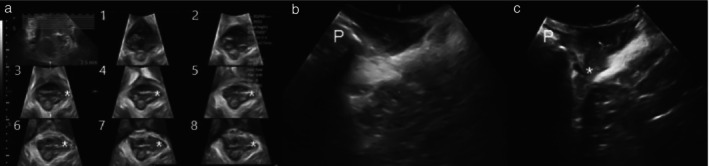

Methods: This was a cross-sectional prospective study of women attending a tertiary urogynecological service between February 2021 and August 2022. All women underwent a standardized interview, pelvic organ prolapse quantification (POP-Q) assessment and four-dimensional transperineal ultrasound. 2D oblique parasagittal ultrasound imaging was performed by rotating the transducer 10-20° from the midline to line up the main transducer axis with the fiber direction of the puborectalis muscle, followed by a full parasagittal sweep of the hiatus at rest. Postprocessing of archived ultrasound volume data was performed at a later date, blinded to all other data. Findings were compared with levator ani assessment results obtained previously using three-dimensional tomographic ultrasound imaging (TUI). Diagnosis of levator ani avulsion on TUI and oblique parasagittal imaging was analyzed for associations with pelvic organ prolapse (POP).

Abstract Image